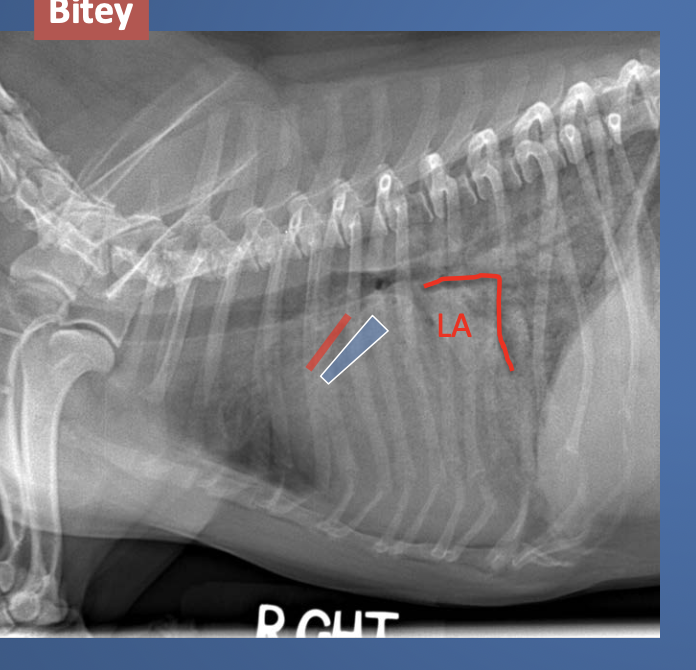

lateral view showed enlarged LA and heart vessels. what is wrong?

DCM. this was lat view